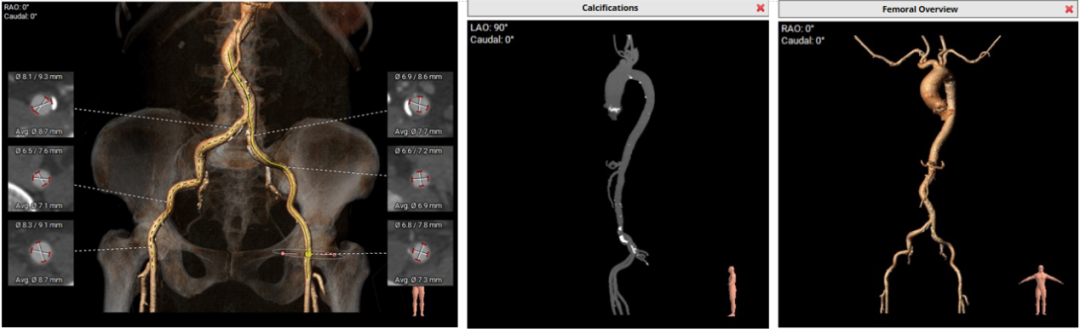

• 主动脉弓、腹主动脉下段、双侧髂总动脉可见散在钙化斑块,双侧髂总动脉局部附壁血栓,腹主动脉、双侧髂总动脉轻度扭曲,入路血管直径尚可。

外周血管入路评估

• 主动脉弓、腹主动脉下段、双侧髂总动脉可见散在钙化斑块,双侧髂总动脉局部附壁血栓,腹主动脉、双侧髂总动脉轻度扭曲,入路血管直径尚可,入路需规范操作,小心通过,避免入路血管相关并发症。

• 右侧股动脉为主入路,左侧股动脉为辅助入路;